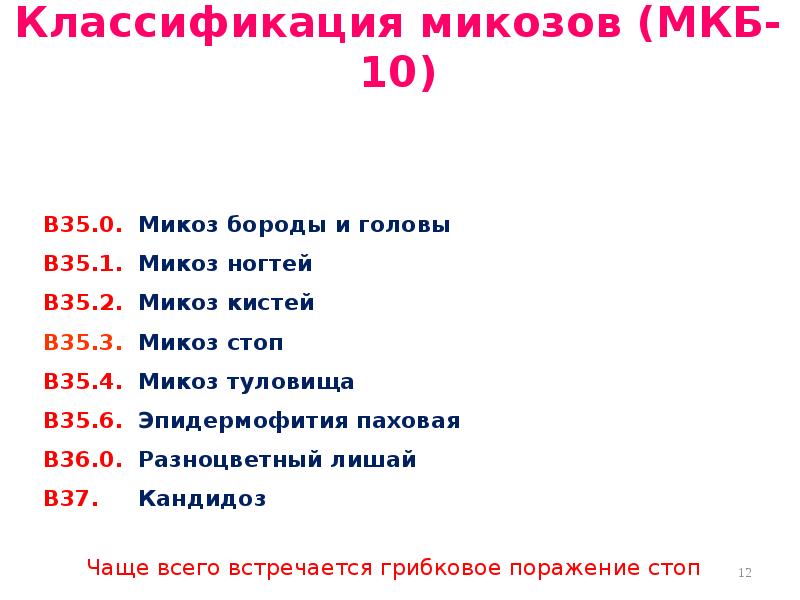

Код мкб 10 атерома головы

Код мкб 10 атерома головы 109 фото